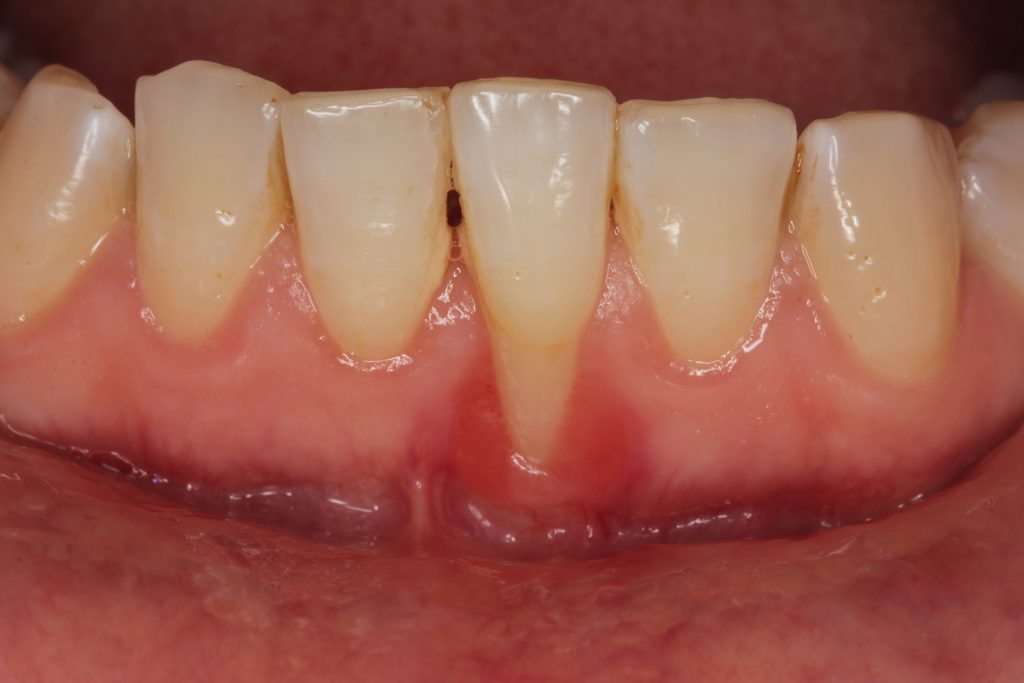

Las encías retraídas son un problema frecuente que ocurre cuando el tejido gingival se desplaza hacia abajo, dejando expuesta la raíz del diente. Esta situación puede provocar sensibilidad dental, mayor riesgo de caries radiculares y afectar la estética de la sonrisa.

La recesión gingival es la pérdida progresiva del tejido de la encía que protege el cuello y la raíz del diente. Puede aparecer en un solo diente o afectar varias zonas de la boca.

Encías retraídas: causas principales

Las causas más frecuentes incluyen:

Cepillado agresivo

Enfermedad periodontal (gingivitis o periodontitis)

Acumulación de placa bacteriana